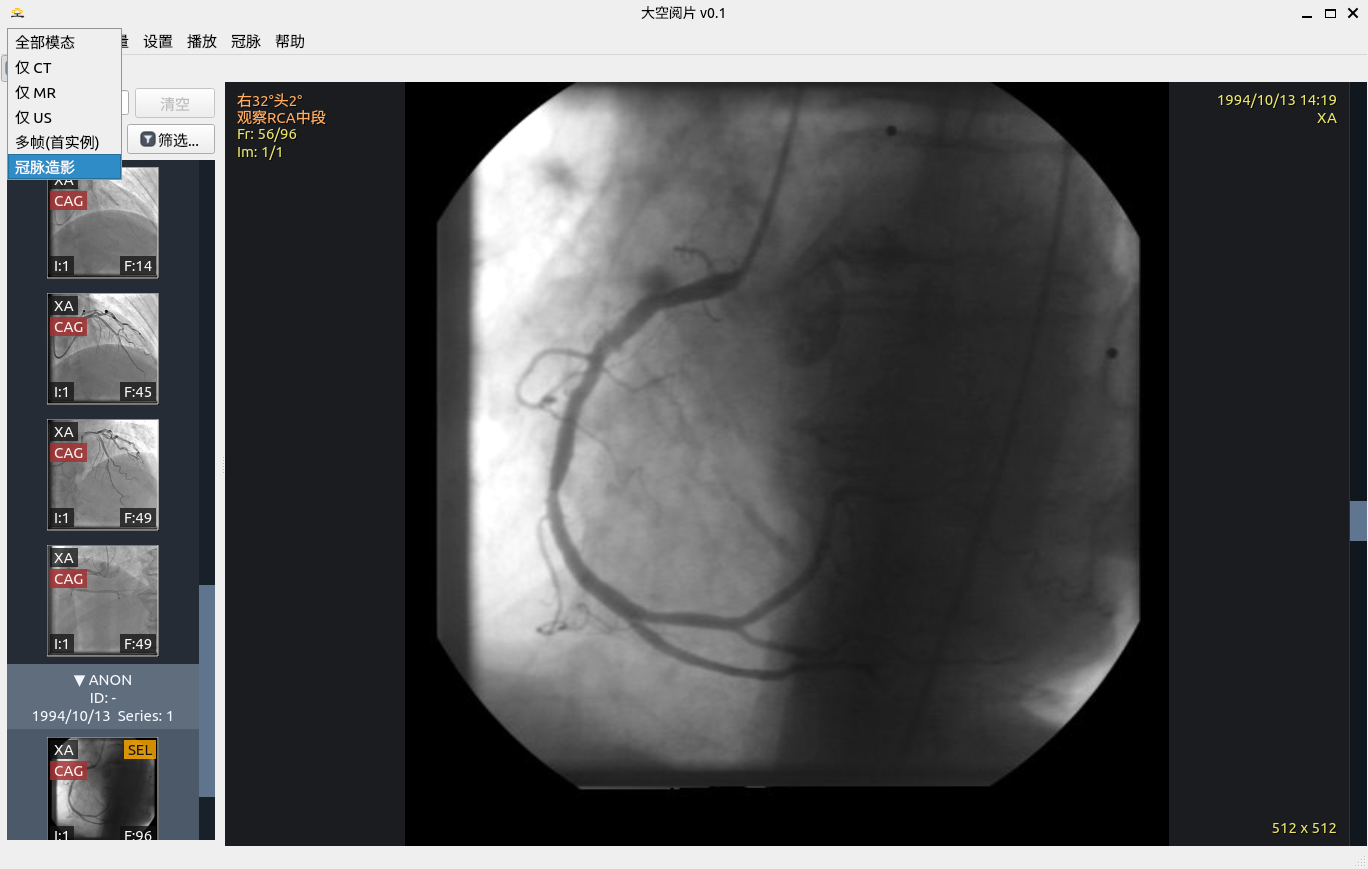

冠脉介入影像筛选

目标血管筛选

2. 冠脉介入影像筛选及目标血管筛选

先把“可做分析的序列”筛对,再进入定量流程,减少无效操作。

• 序列级规则筛选:结合 Modality、ImageType、描述信息与实例结构。

• 人工判定与算法判定双轨:可标记冠脉/非冠脉并随时回退。

• QCA 入口与序列资格联动,避免误入分析流程。